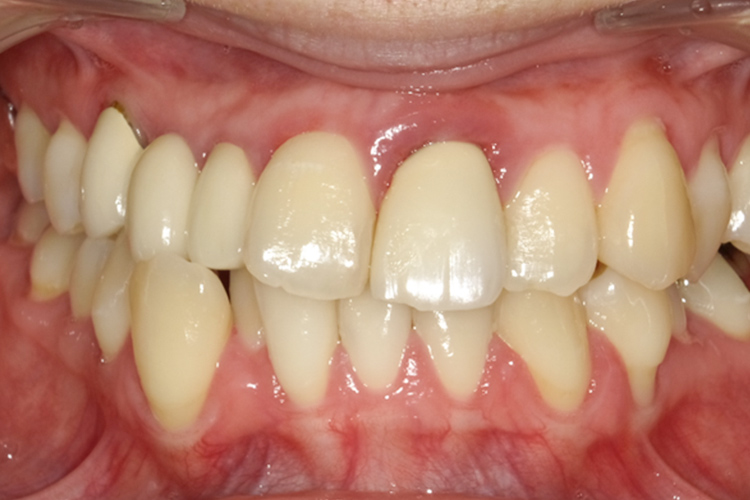

治療前

治療後